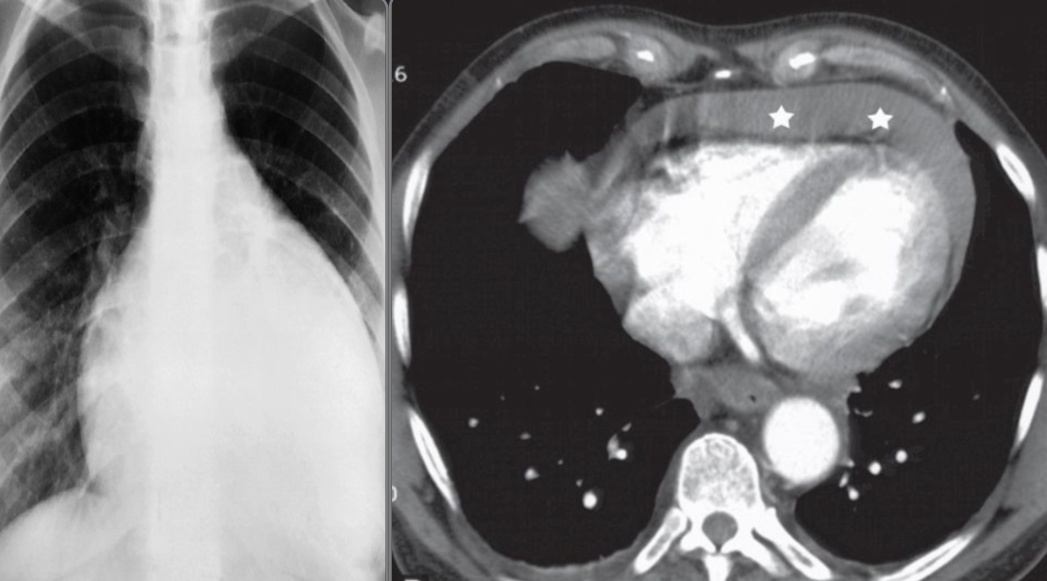

A. Imaging modality Plain X-ray / CT

B. Findings or description Cardiomegaly, globular shape, fluid collection around heart

C. What is the most likely diagnosis ? Pericardial effusion

- CT thorax (with contrast; axial view)

- A mucosal flap can be seen dividing the lumen of the ascending and descending aorta.

- This radiological appearance confirms an aortic dissection.